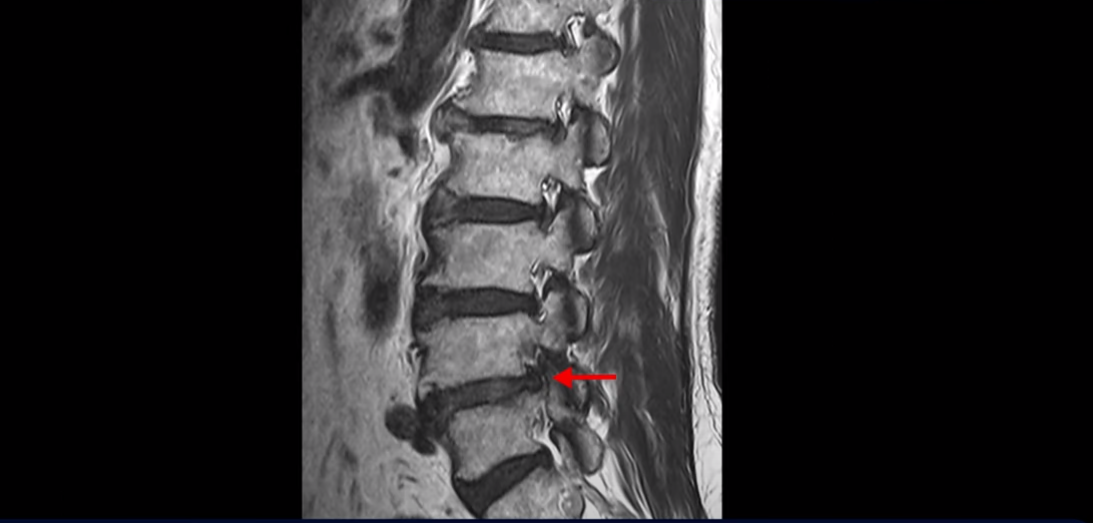

먼저 이분 MRI를 보면서 간단히 설명드린 후 어떻게 신경이 눌려서 반드시 수술해야 한다는 환자나 이 환자분처럼 수술이 필요하지만 나이가 많아서 못한다고 하는 환자분을 수술 없이 치료할 수 있는지 또 치료는 어떻게 하는지 자세히 설명드리겠습니다.

이분 MRI를 보면 척추의 여러 마디가 퇴행이 진행되어 안 좋습니다.

특히 4번 5번 마디가 제일 안 좋은데 보시다시피, 하얗게 보여야 될 신경이 거의 안 보일 정도로 척추관이 좁아져 있습니다.

이분은 허리도 아프지만 왼쪽 엉덩이와 다리가 너무 심하게 저리고 아팠는데 역시나 왼쪽 신경 가지가 빠져나가는 구멍이 막혀 있어서 매우 어둡게 보입니다.